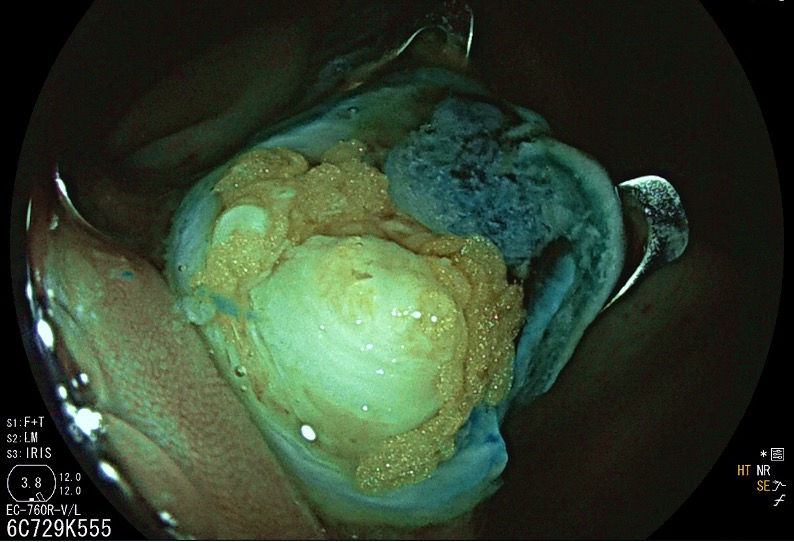

Hybrid endoscopic full-thickness resection of an appendicular laterally spreading tumour - 2.º Classificado (Fotografia)

Maria Manuela Estevinho, Jaime Rodrigues, Rolando Pinho, Edgar Afecto, João Correia, Teresa Freitas

Centro Hospitalar Vila Nova de Gaia/Espinho - Serviço de Gastrenterologia

A 69-year-old woman, with no relevant medical history, was referred to our department after identification, in screening colonoscopy, of a laterally spreading tumour, granular homogenous, with 30mm, centred in the appendiceal orifice. The peripheral portion of the lesion was removed by piecemeal mucosal resection, while endoscopic full-thickness resection (EFTR, Ovesco Endoscopy) was performed on the central portion invading the appendix. Follow-up was uneventful. The EFTR specimen contained the transected appendix; histological analysis showed a tubulovillous adenoma with low-grade dysplasia. EFTR is a minimally invasive alternative to resect appendiceal lesions; this hybrid approach enables exceeding the size limit of the device.